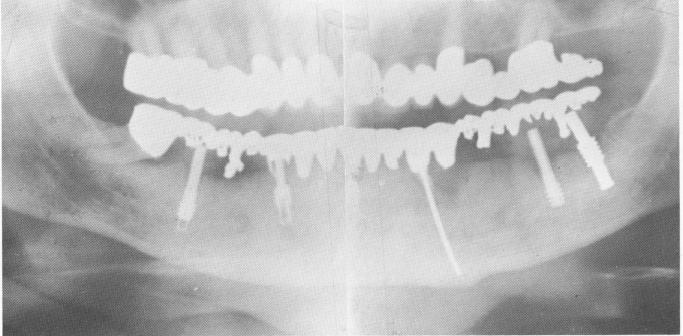

Fig. 13-32. A 3-year postoperative Panorex roentgenogram shows the endodontic implant stabilizer and the implants. Some bone resorption is evident around the left first implant extending downward from the alveolar crest. Also, an infrabony pocket exists along part of the mesial wall of the remaining right molar. The patient, however, has been enjoying eating and chewing for the past 3'/rz years. There is no mobility.